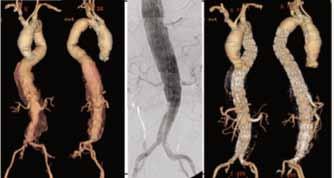

The Emerging Role of Fenestrated and Branched Aortic Endografts in the Treatment of Complex Aortic Aneurysms

Endovascular repair of abdominal and thoracic aneurysms has become widely accepted, especially for elderly and high-risk patients, due to decreased blood loss, shorter recovery, and decreased morbidity and mortality associated with these procedures. However, approximately half of patients with abdominal aortic aneurysms are not suitable candidates for endovascular repair using commercially available stent grafts as a result of unfavorable anatomy, including juxtarenal, paravisceral, hypogastric and thoracoabdominal involvement and short or angulated aortic necks.

Conventional open-surgical repair may be appropriate for healthy patients contraindicated for endovascular procedures, but those with large aneurysms or concomitant conditions that affect cardiac, pulmonary or renal performance have a high risk of operative complications. For these patients, fenestrated and branched stent grafts may offer a viable option.

Fenestrated and branched stent grafts were designed to extend the proximal sealing zone so that patients with short or absent aortic necks can be considered for total endovascular repair.

These devices are similar to other stent grafts, but with the addition of reinforced fenestrations or cuffed branches to allow the incorporation of renal and visceral arteries without compromising sealing requirements. First used in 1996, their design, as well as implantation techniques, have since been refined considerably, and they are now used in select high-risk patients with complex aneurysmal presentations throughout the entire length of the aorta.

Unfortunately, these devices are not yet commercially available in the United States. In countries where they are available, the grafts must be customized for each patient, a process that can take up to 12 weeks, during which time some patients will experience a rupture of their aneurysm. As an alternative, a few vascular surgeons throughout the country have been custom-making fenestrated and branched stent grafts since 2007 using currently available components.

The new fenestrated and branched aortic stent graft program established at Emory University Hospital is part of a broader effort led by veteran Emory vascular surgeons Thomas F. Dodson,

MD, Karthikeshwar Kasirajan, MD, and Ravi K. Veeraswamy, MD, to provide comprehensive surgical and endovascular treatment options for a full range of aortic aneurysm presentations. Joseph J. Ricotta II, MD, recently joined the Emory Division of Vascular Surgery & Endovascular Therapy to help establish the new program. Before coming to Emory, Dr. Ricotta performed more than 100 fenestrated and branched endografts at the Mayo Clinic. Emory is currently one of only a few institutions in the country and the only one in the Southeast that offers these investigational procedures.

Fenestrated and branched endografts appear destined to play a key role in the management of complex aortic aneurysms. Shortand mid-term data have shown that these devices are both safe and effective in treating carefully selected patients, with low incidence of complications. Additional data are needed to substantiate these results, and Emory is poised to participate as a primary site in upcoming trials of these innovative devices.

Three-dimensional CTA of a type II thoracoabdominal aortic aneurysm before and after endovascular repair using a surgeon-modified fenestratedbranched stent graft with branch stenting to the celiac, superior mesenteric and bilateral renal arteries. Image courtesy of Joseph J. Ricotta II, MD. A surgeon-modified fenestrated stent graft immediately prior to implantation. Image courtesy of Joseph J. Ricotta II, MD